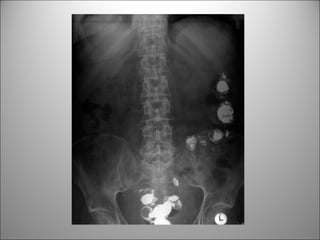

TEJIDO BLANDO

• Visión limitada de estructuras-órganos

• Puede verse +/-

– Hígado

– Bazo

– Riñones

– Psoas

– Vejiga

– Bases pulmonares